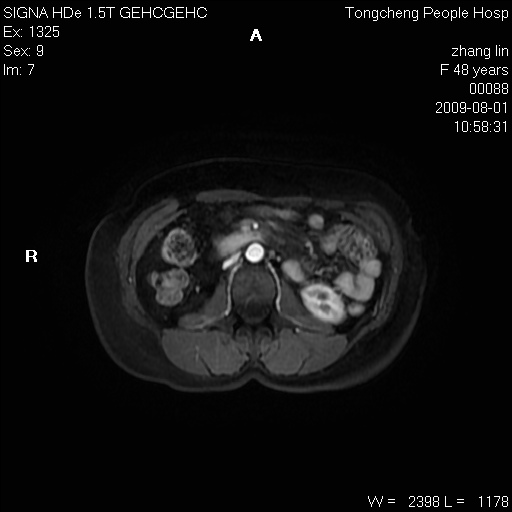

女,48岁。健康体检,彩超发现右肾占位性病变。平素健康。

临床诊断:右肾占位性病变,性质待定(囊肿?肿瘤?)。

上中腹部mr平扫+增强扫描,图像如下:

右肾上极见一类圆形病灶,t1wi呈等信号t2wi呈等高混杂信号,三期增强无强化,边界清---考虑囊肿出血。

同反相位均表现为等信号,病变无强化,考虑含蛋白的囊肿可能,弥散加权相或许有些帮助,

慢性胆囊炎